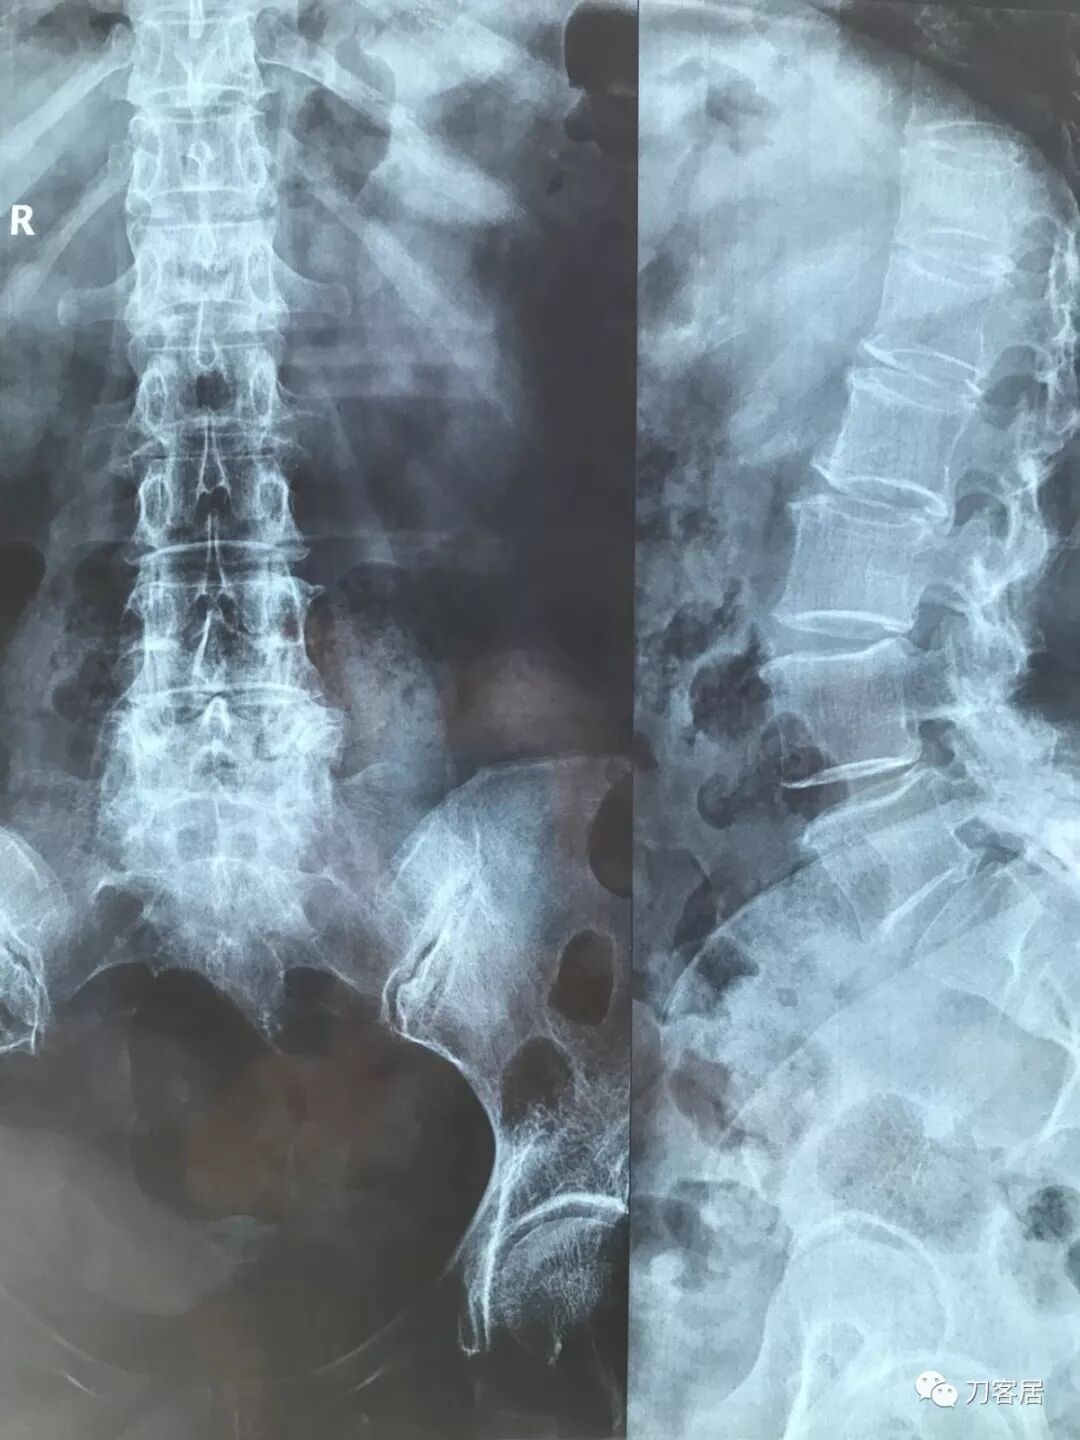

拍片子时,如果一张片子上有两张图像的时候,合起来拍一张(图15),分开再各拍一张(图16,图17)

图16

图17